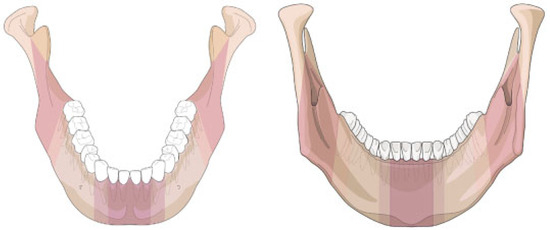

Figure 3.

Illustration of mandibular edentulism and atrophy. (A) "Atrophy grid" superimposed on a fully dentulous mandible with permanent teeth. The mandibular body regions, the para–symphsis and the transitional zones depicted as vertical sectors are maintained unchanged. To allocate the fractures to a topographical site the borderlines/frontiers of the region are transferred to the edentulous situation. (B) Left side: Moderate level of atrophy (code 2) on both the body regions, but no atrophy (code 0) in the parasymphysis. Right side: Severe level of atrophy (code 3) over the whole arch of the edentulous mandible ("pencil bone").